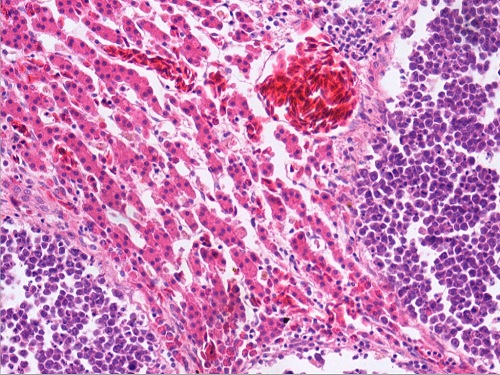

鸡肝淋巴肉瘤(肝细胞被压迫萎缩,肿瘤灶内为成淋巴细胞)

鸡肝淋巴肉瘤